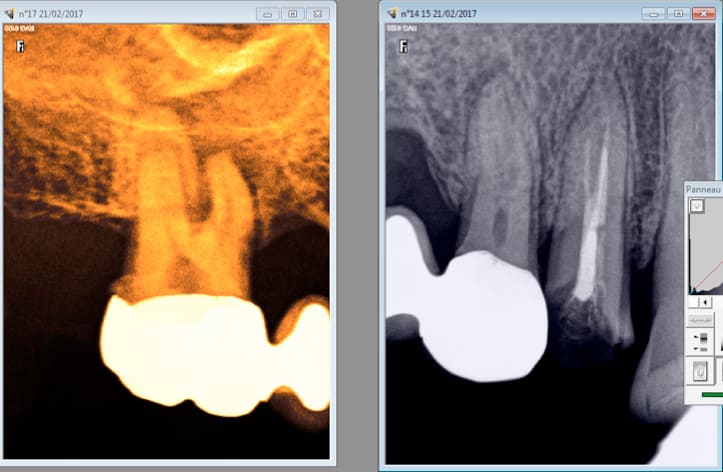

IC coiffe en 2006 sur cette 36, RTE que du distal. 2017 pÚche dans les mésiaux RTE de tous les canaux empreinte.

Je suis assez satisfait c'est propre au niveau paro, meme aprÚs séance de barbecue en 2006. -)

En 2006 avec les pro tapers c'était moyen moyen. Avec le réciproc R25 blue ca rentre comme dans du beurre. C'est pas compliqué c'est comme une bio sans l'anesthésie.

L'inlay core a dégagé en 5 secondes au coronaflex.

Ca s'appelle "fidéliser" -))))

C'est pas la pulpe. Je suis content de ma "fidélisation" surtout quand j'arrive à trouver le MV2 6 ans aprÚs. Comme ca on passe 2 couches de peinture. -)

C'est la pulpe, c'est la pulpe.

Pas de réponse au froid. Curieux non ? -)))

C'est la pulpe c'est la pulpe.

Festival aujourd'hui ! -)))